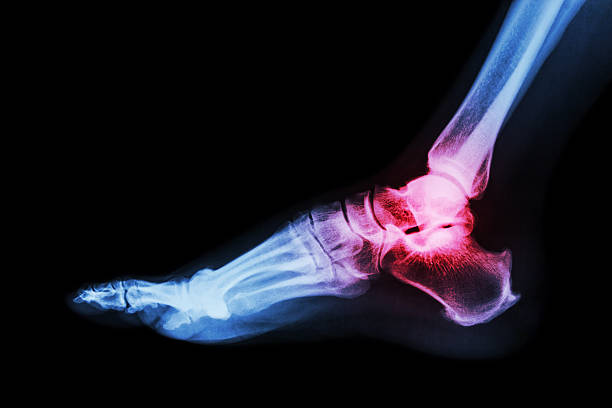

Foot and ankle surgery is performed to treat a variety of conditions, such as fractures, arthritis, tendon injuries, deformities, and chronic pain. Common procedures include repairing broken bones, correcting misalignments like flat feet or bunions, and addressing issues like Achilles tendon ruptures or ankle instability. Surgery can be performed using open or minimally invasive techniques, depending on the severity and location of the problem. Recovery often involves physical therapy to restore mobility, strength, and function. The goal of foot and ankle surgery is to alleviate pain, improve stability, and enable patients to return to normal activities with enhanced mobility.